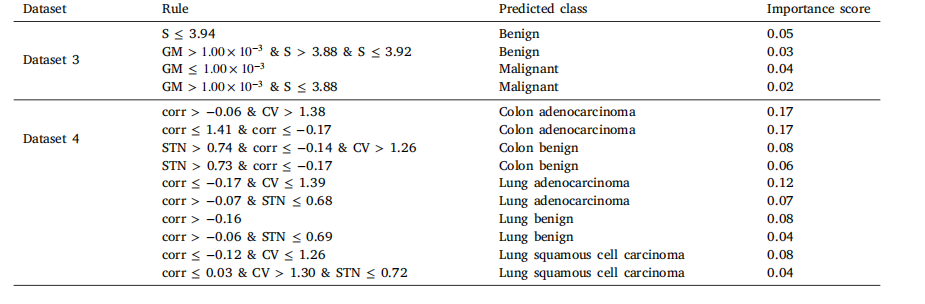

Table 12Decision tree rules for top two datasets based on classification performance.

表12 基于分类性能的前两个数据集的决策树规则。

Table 13RuleFit rules for top two datasets based on classification performance.

表13 基于分类性能的前两个数据集的RuleFit规则。